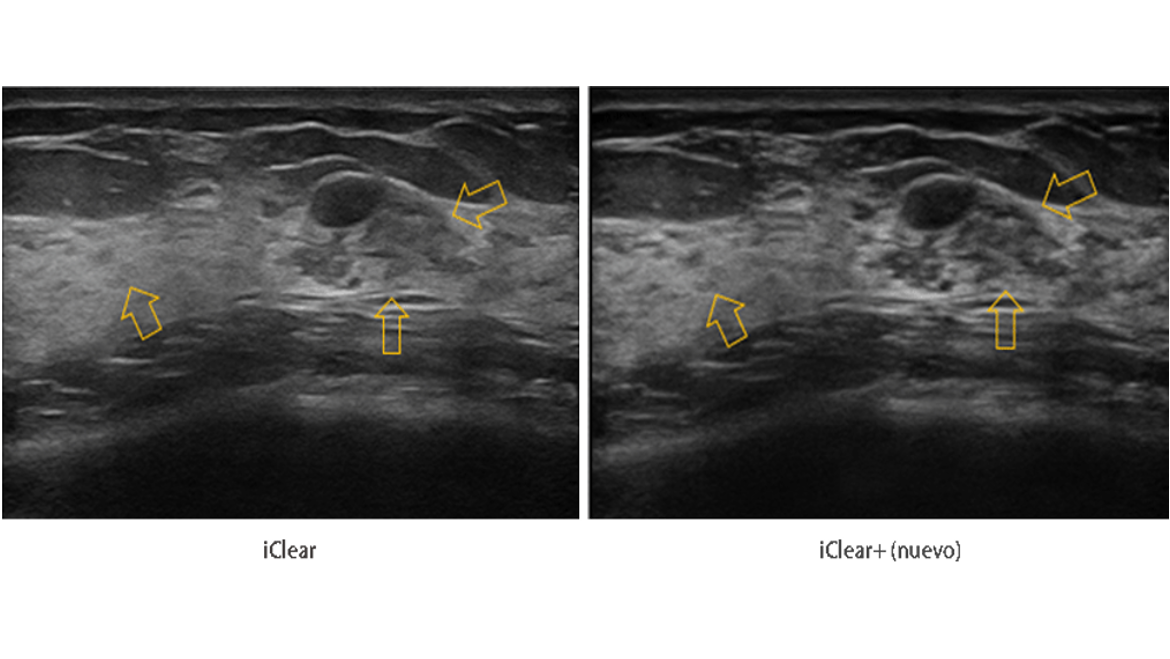

ImГЎgenes ClГӯnicas